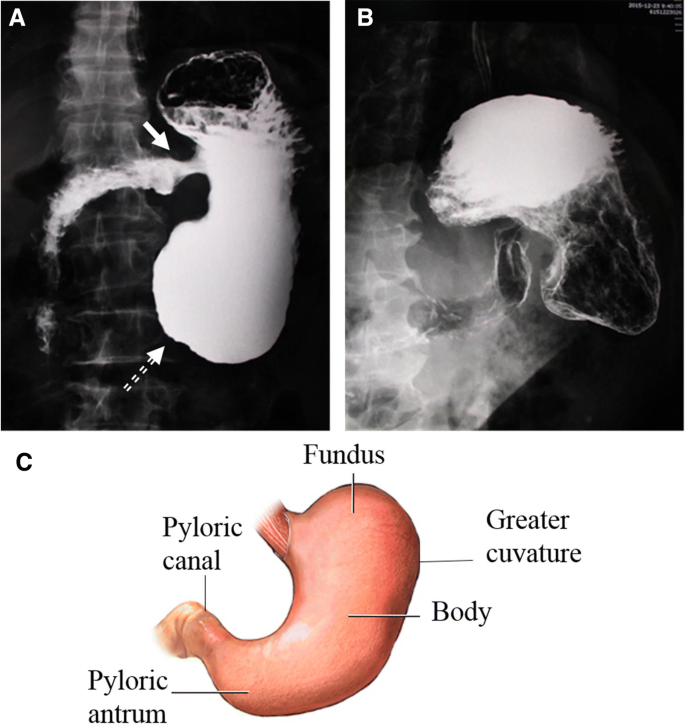

Gastric cardia radiology. Diagnostic centers of america dca is a leading diagnostic imaging facility offering a full array of imaging services in palm beach county florida. We have five state of the art radiology imaging centers in boca raton boynton beach delray beach and wellington florida. The gastric cardia is characterized on barium stud ies by three or four stellate folds that radiate to a central point at the gastro esophageal junction also known as the cardiac rosette fig 2 12. Variations and benign influences may closely resemble the more dangerous lesion.

Cain jc jordan gl jr comfort mw gray hk. J am med assoc. The gas tric fundus is dened as the portion of the stomach craniad to the gastric car dia. Commonly accompanying this are abnormally dilated short gastric veins which pass from the splenic vein to encircle the gastric fundus and form gastric fundal varices.